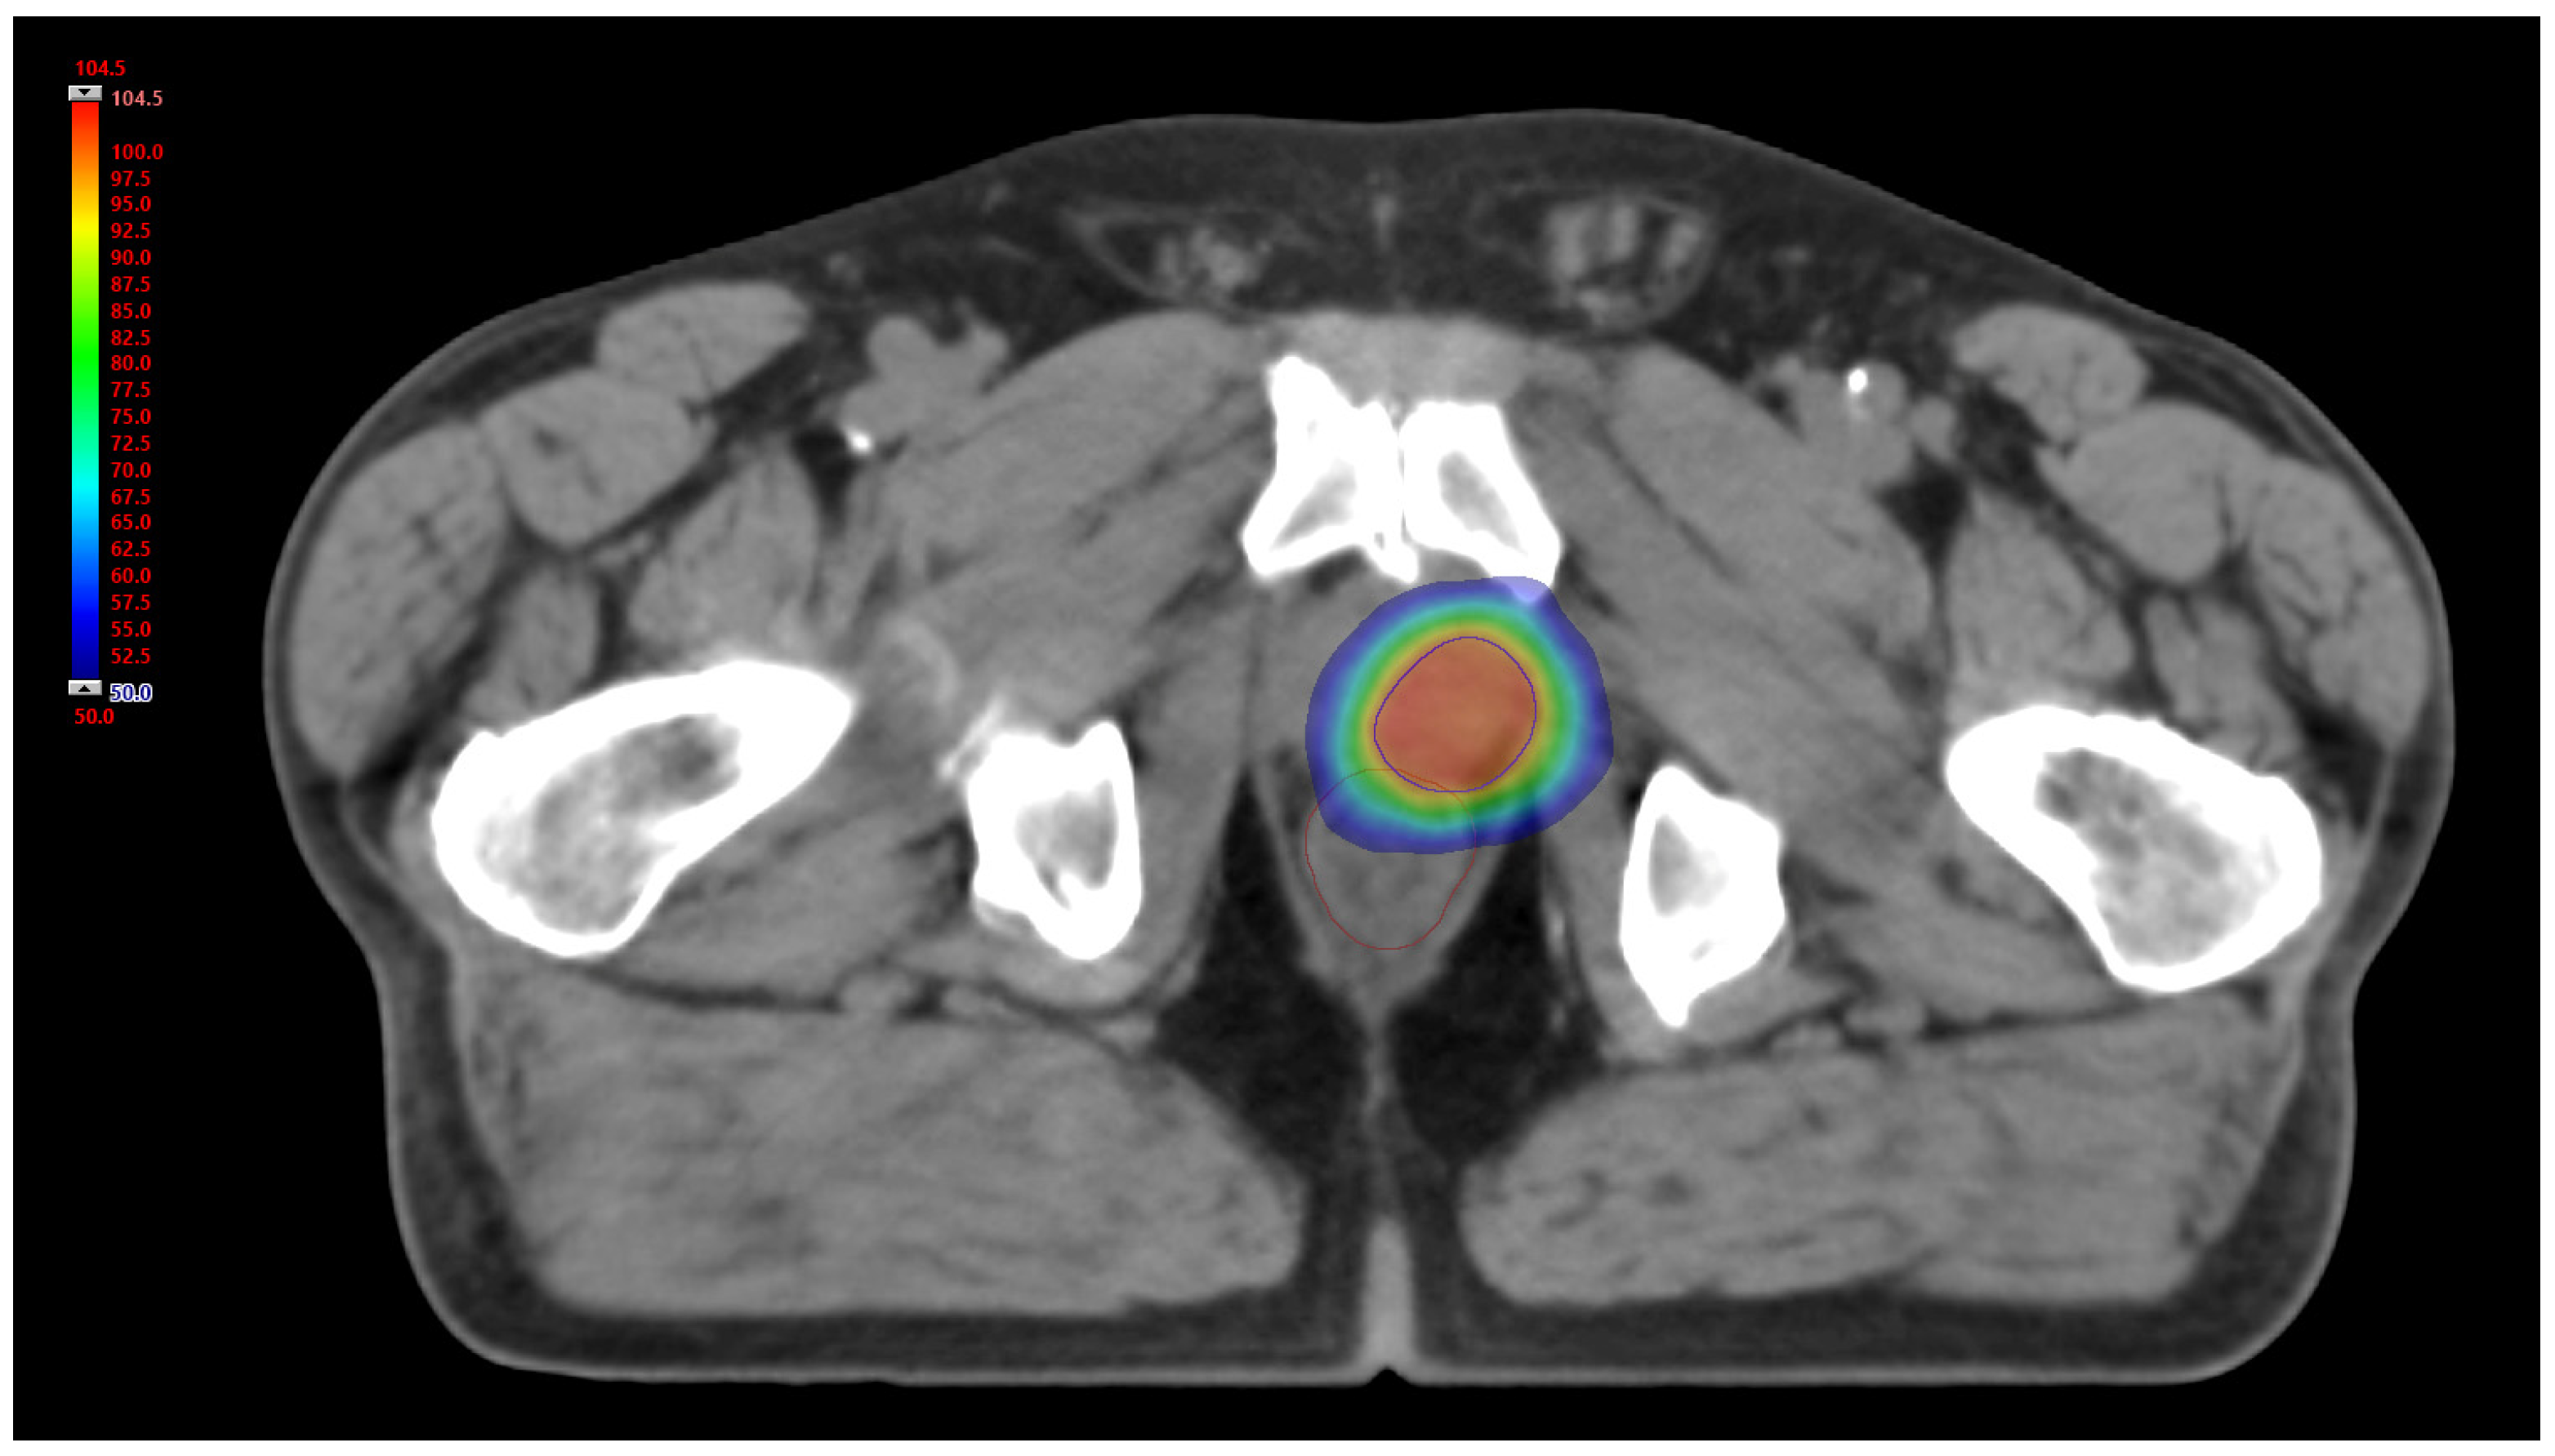

As already extensively described [36], PPR treatment was performed delivering a volumetric modulated arc therapy (VMAT) technique with a course scheme of 35 Gy in seven daily fractions of 5 Gy, five fractions/week (Figure 2); considering an alpha-beta ratio of 1.5 Gy, the total BED at the target was 151.7 Gy [40]. All patients were imaged with a non-contrast-enhanced pre-treatment CT using a 32-slice scanner (Toshiba Aquilion LB, Toshiba Medical Systems Europe, Zoetermeer, the Netherlands). The gross target volume (GTV) was defined with the aid of the (11C)-choline PET as the volume delineated with a semi-automated technique using a fixed threshold of 40% of the maximum signal intensity. To reduce inter-observer variability, minimal manual corrections of the GTV borders were performed to take into account anatomical differences due to possible sub-optimal spatial registration between different image modalities. The dose distributions were calculated on a resolution grid of 2.5 mm or less with Eclipse treatment planning system (TPS) version 13.6, using the Anisotropic Analytical Algorithm version 13.6.23 (Varian Medical System, Palo Alto, CA, USA). For each patient, PET and CT images, together with the dose distributions and GTV contours, were saved in the digital imaging and communications in medicine (DICOM) format. The following analysis, including data conversion, image post processing, feature calculation and model training and validation were performed in Matlab R2021b version: 9.12.0.1927505 R2022a (The MathWorks, Inc., Apple Hill Drive Natick, MA, USA).

Figure 2. Axial view of 3D relative dose distribution (%). Blue line: PTV; brown line: rectum.